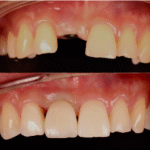

มาจากต่างประเทศ มีเวลาอยู่ไทยแค่ 2 เดือน มีปัญหา

ไม่มีฟันเคี้ยว ครอบเก่าฟันหน้าไม่สวย คุณหมอบอกต้อง

ทำใหม่เกือบทั้งปาก ครอบฟัน 20 ซี่ รากเทียม 4 ซี่ ทำเสร็จแล้วคุ้มค่ามาก ยิ้มสวย ใช้งานได้ดีเลยค่ะ — คุณนิจรินทร์